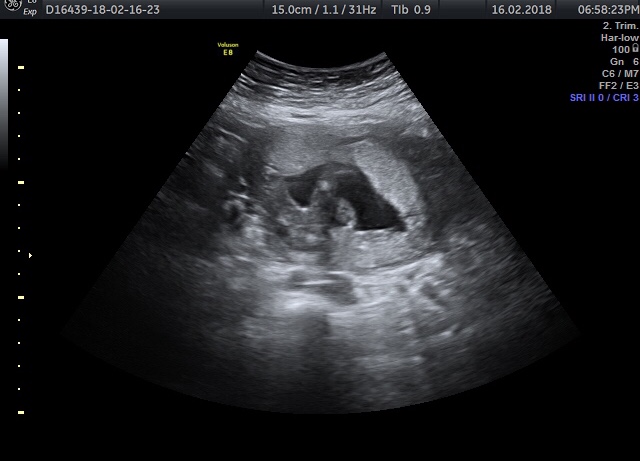

I was told girl again (after being told at 16w) saw lines in the scan but on the pics I was given there are no magic 3 lines 🙄 would you be happy to say girl or wait and try again on another scan?!Attachment 38836Attachment 38837Attachment 38838